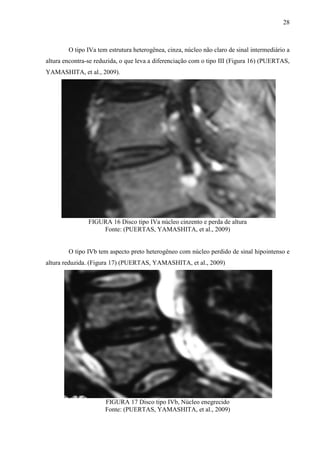

O tipo IVa tem estrutura heterogênea, cinza, núcleo não claro de sinal intermediário a

altura encontra-se reduzida, o que leva a diferenciação com o tipo III (Figura 16) (PUERTAS,

YAMASHITA, et al., 2009).

FIGURA 16 Disco tipo IVa núcleo cinzento e perda de altura

Fonte: (PUERTAS, YAMASHITA, et al., 2009)

O tipo IVb tem aspecto preto heterogêneo com núcleo perdido de sinal hipointenso e

altura reduzida. (Figura 17) (PUERTAS, YAMASHITA, et al., 2009)

FIGURA 17 Disco tipo IVb, Núcleo enegrecido